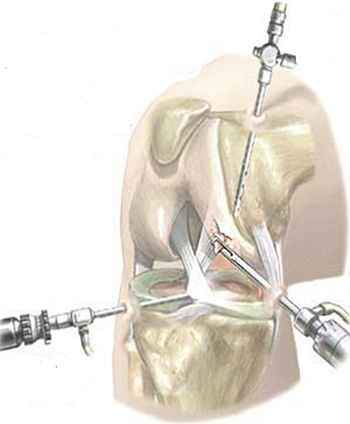

Beszél a hatása a műtét, érdemes megjegyezni, hogy formáját ölti arthroszkópiával és használt rekonstrukció elpusztult meniszkusz vagy szalagok. Ha nincsenek komplikációk, majd miután egy ilyen eljárás, a beteg egyre jobb.

Artroszkópiás - egy bevált módszer együttes hasznosítás nagy hatékonysággal